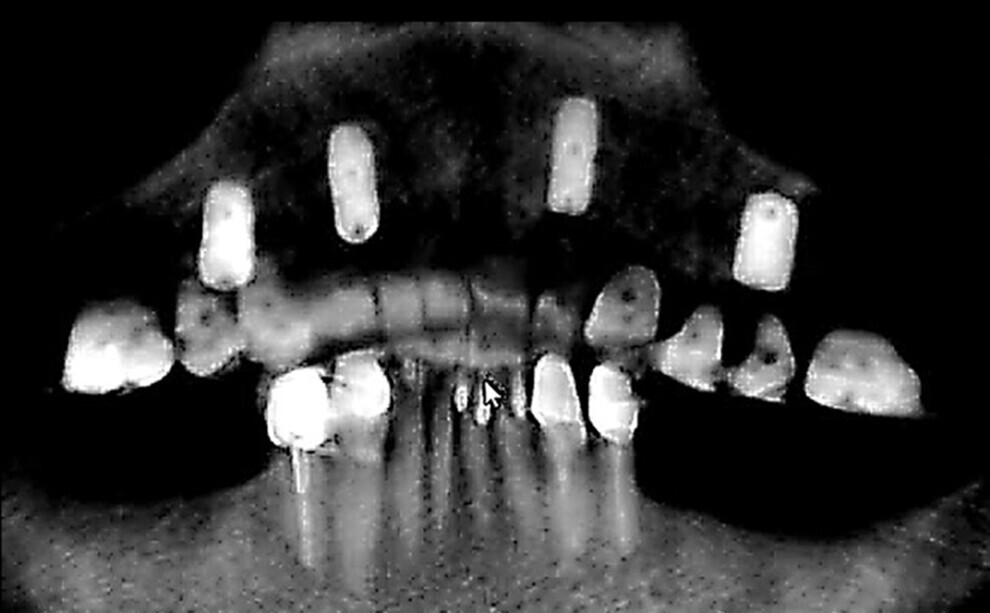

The implants were placed 4–5 mm below the alveolar crest as planned to provide adequate room for the Atlantis Conus abutments. The fixation screws and the surgical guide were removed from the mouth. An incision was made at the centre of the ridge and the soft tissue flapped to expose the crestal bone and some of the buccal and palatal bone. A surgical carbide bur was then utilised to reduce the crestal bone across the arch to 1 mm from the platform of the implants at the four sites. Alveolar crestal reduction was performed after implant placement to avoid loss of stability of the surgical guide. Cover screws were placed, and the soft tissue re-approximated and fixated with #4-0 nylon sutures in an interrupted pattern. The patient’s old maxillary denture was relined with EasySoft liner (Karlin) to accommodate the reduction in crestal height performed. A panoramic radiograph was taken to document the implant placement (Fig. 17).

Fig. 17: Panoramic radiograph taken after implant placement.